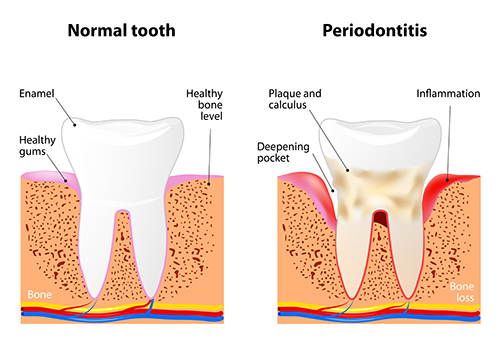

Periodontitis is a severe gum infection that causes damage to the soft tissues and if left untreated can damage the bone that holds your teeth leading to tooth loss. Gum disease is common but you can prevent it by maintaining proper hygiene and regular dental checkups. The chances of the treatment increase when you strictly follow the daily dental regime. Also, it reduces the chances of getting this disease. Get the treatment from emergency dentistry if the infection is severe.

Usually, periodontitis begins with plaque formation. Plaque is a sticky substance formed due to the growth of bacteria. If you don’t treat it in time, the plague eventually advances to periodontitis.

Plaque hardens under your gum line leading to tartar if it stays for a longer time on your teeth. Proper Brushing and flossing can help extract plaque. But it can reform quickly. The longer it stays on your teeth, the more damage like; Tooth Infection can cause.

The preliminary stage of infection resembles gingivitis but the infection spreads from gums to ligaments and bone, supporting the tooth. The tooth starts loosening due to loosened ligaments. This is followed by a fall-out of the tooth, eventually. Periodontitis treatment is one of the main causes of tooth fall-out. Usually, teenagers are prone to the disease and if it stays for a longer time in their mouth, it may terribly affect the gums and the tooth. Plaque and tartar gather at the base of the teeth and end in the development of gum pockets between the teeth.